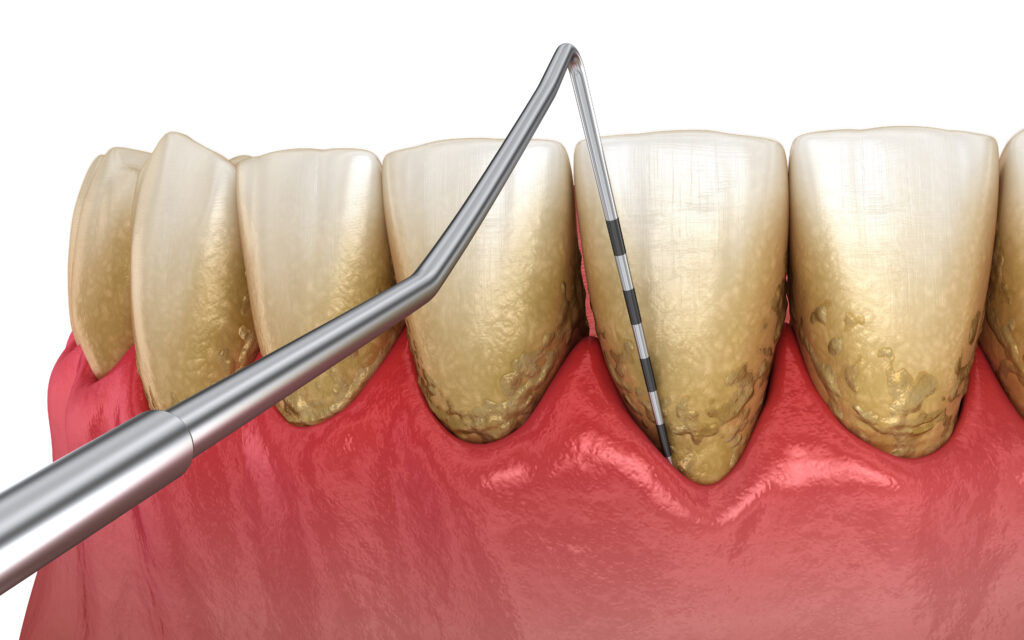

Dotykanie sondą periodontologiczną okolicy przyzębia pozwala ocenić:

- obecność kieszonek przyzębnych oraz ich głębokość

- kieszonki dziąsłowe > 3,5 mm świadczą o chorobie przyzębia